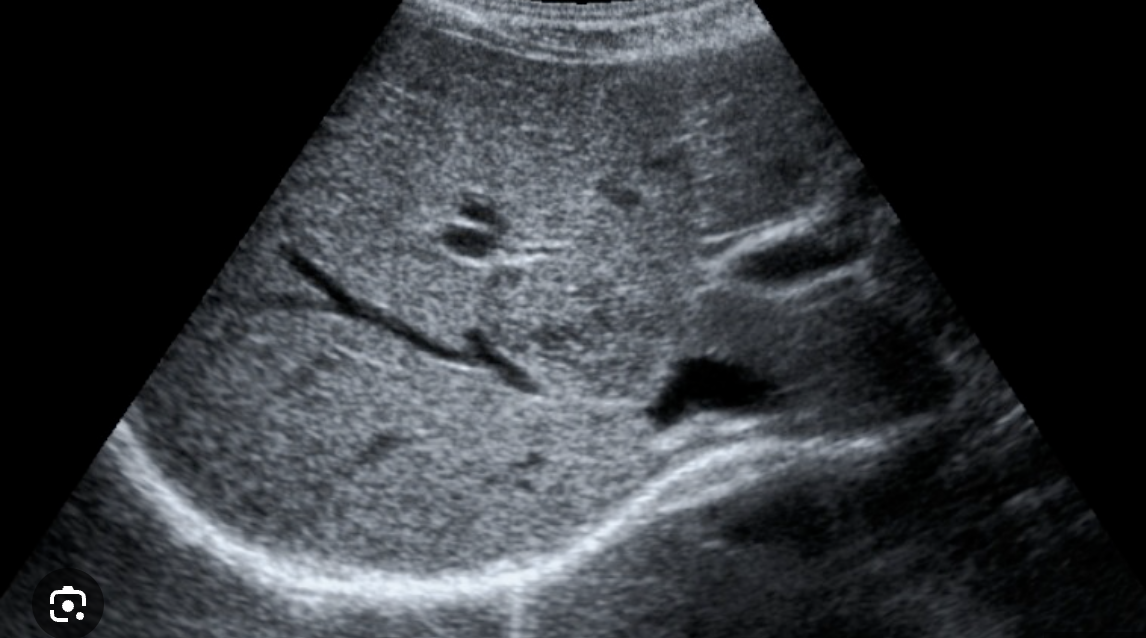

Congestion → increased pressure in IVC and hepatic vein(s) usually by right-sided heart failure

2D US appearance: dilation of IVC and one or more hepatic veins (IVC greater than 3 cm diameter and hepatic veins greater than 13 mm)

PW: IVC loses “houndstooth” waveform and turns mildly undulating

DDX: budd-chiari (hepatic vein thrombosis/obstruction, but there is no outflow obstruction in congestion)